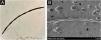

The proband (II-2) was a 30-year-old woman. She developed sparse, short, and fragile hairs with apopecia since infancy (Fig. 1A). There were numerous keratotic follicular papules on her occipital area (Fig. 1B). The secondary hair, eyebrow, eyelashes, fingernails, and systemic examination were all normal. Dermoscopic examination showed typical beading and nodes (Fig. 1C). Under light microscopy, the hair shaft showed characteristic elliptical nodes and intermittent constrictions (Fig. 2A). Scanning electron microscopy revealed that cylindrical hair had a segmental structure with periodic nodules and narrow parts: width of the nodules was 0.09‒0.11 mm and width of the constriction was 0.05‒0.08 mm. The parallel longitudinal ridge and groove could be seen on the surface similar to the bark-like appearance, and an erosion-like structure appeared on the cross-section (Fig. 2B). Histopathological examination of the affected scalp showed hyperkeratosis, decreased hair follicle density, infiltration of chronic inflammatory cells around the follicular unit with plugging (Fig. 3).